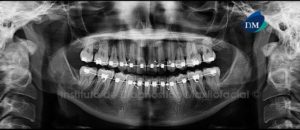

Paciente masculino, 54 años es referido al Instituto de Diagnóstico Maxilofacial para planificación de cirugía guiada con el objetivo de colocar implantes dentales en el